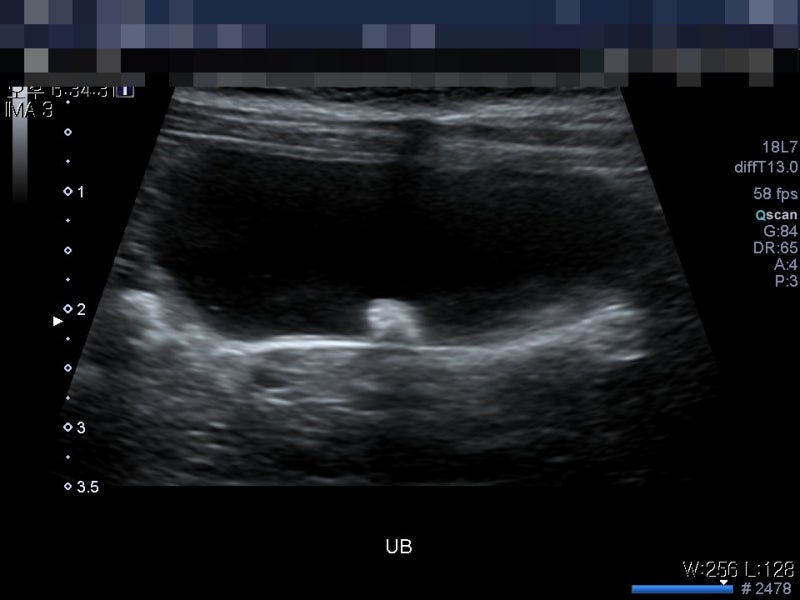

강아지 누렁이가 몇 번 피 묻은 소변을 본 것 외에 아파하지는 않으니(결석도 작고 다수) 그래서 우선 약 처방을 받고(이게 항생제 같은 건가?) #결석사료를 사서 수술은 마지막 보류로 남기고 그 전에 자연치유 관리에 들어가기로 했다.

#개의 방광결석증상 보통 이 증상이 소변을 거의 볼때쯤 위와 같이 피가 섞여 나온다; (이번에는 좀 진해서 놀랐다;;)

소변이 나오고 안의 결석이 방광벽을 긁기 때문이라고 들었다. 사람들도 결석때문에 기절할정도로 아프다고 한사람도 있다던데;;